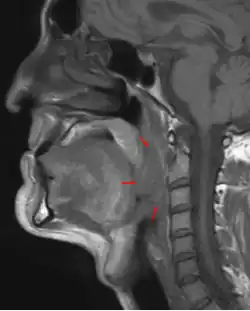

3D medical illustration showing the cancer formation in the tissues of the oropharynx | |